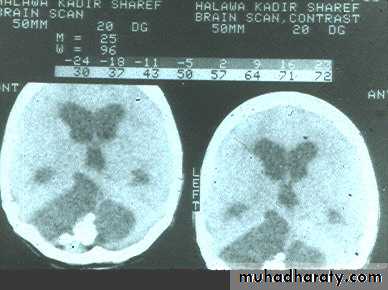

Hydrocephalous

2 types

Obstructive ( non – communicating )

Craniophyrengioma

Medulloblastoma

Ependymoma

Aquiduct stenosis , comments cause of obstruction being congenital in nature .

Non –obstructive ( communicating )

No obstruction of the ventricular pathway , but the absorption of the csf at the level of arachnoids' granulation is occluded secondary to lodge by blood clot or inflammatory cell or infection post meningitis most commonly to occur post SAH .